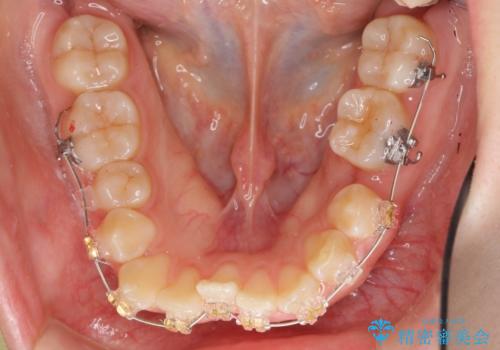

よくある悩み 前歯が裏に2本入っているのを治したい

- 前歯が2本裏に入ってしまっているのを治したいとのことでした。

プラン1:上の正中をずらさない・・・上下左右4本抜歯

プラン2:上の正中は少し左にずれる・・・左の上下2本抜歯

を提案し、プラン2を選択されました。

最小限の抜歯により矯正ができたと、喜んでいただきました。